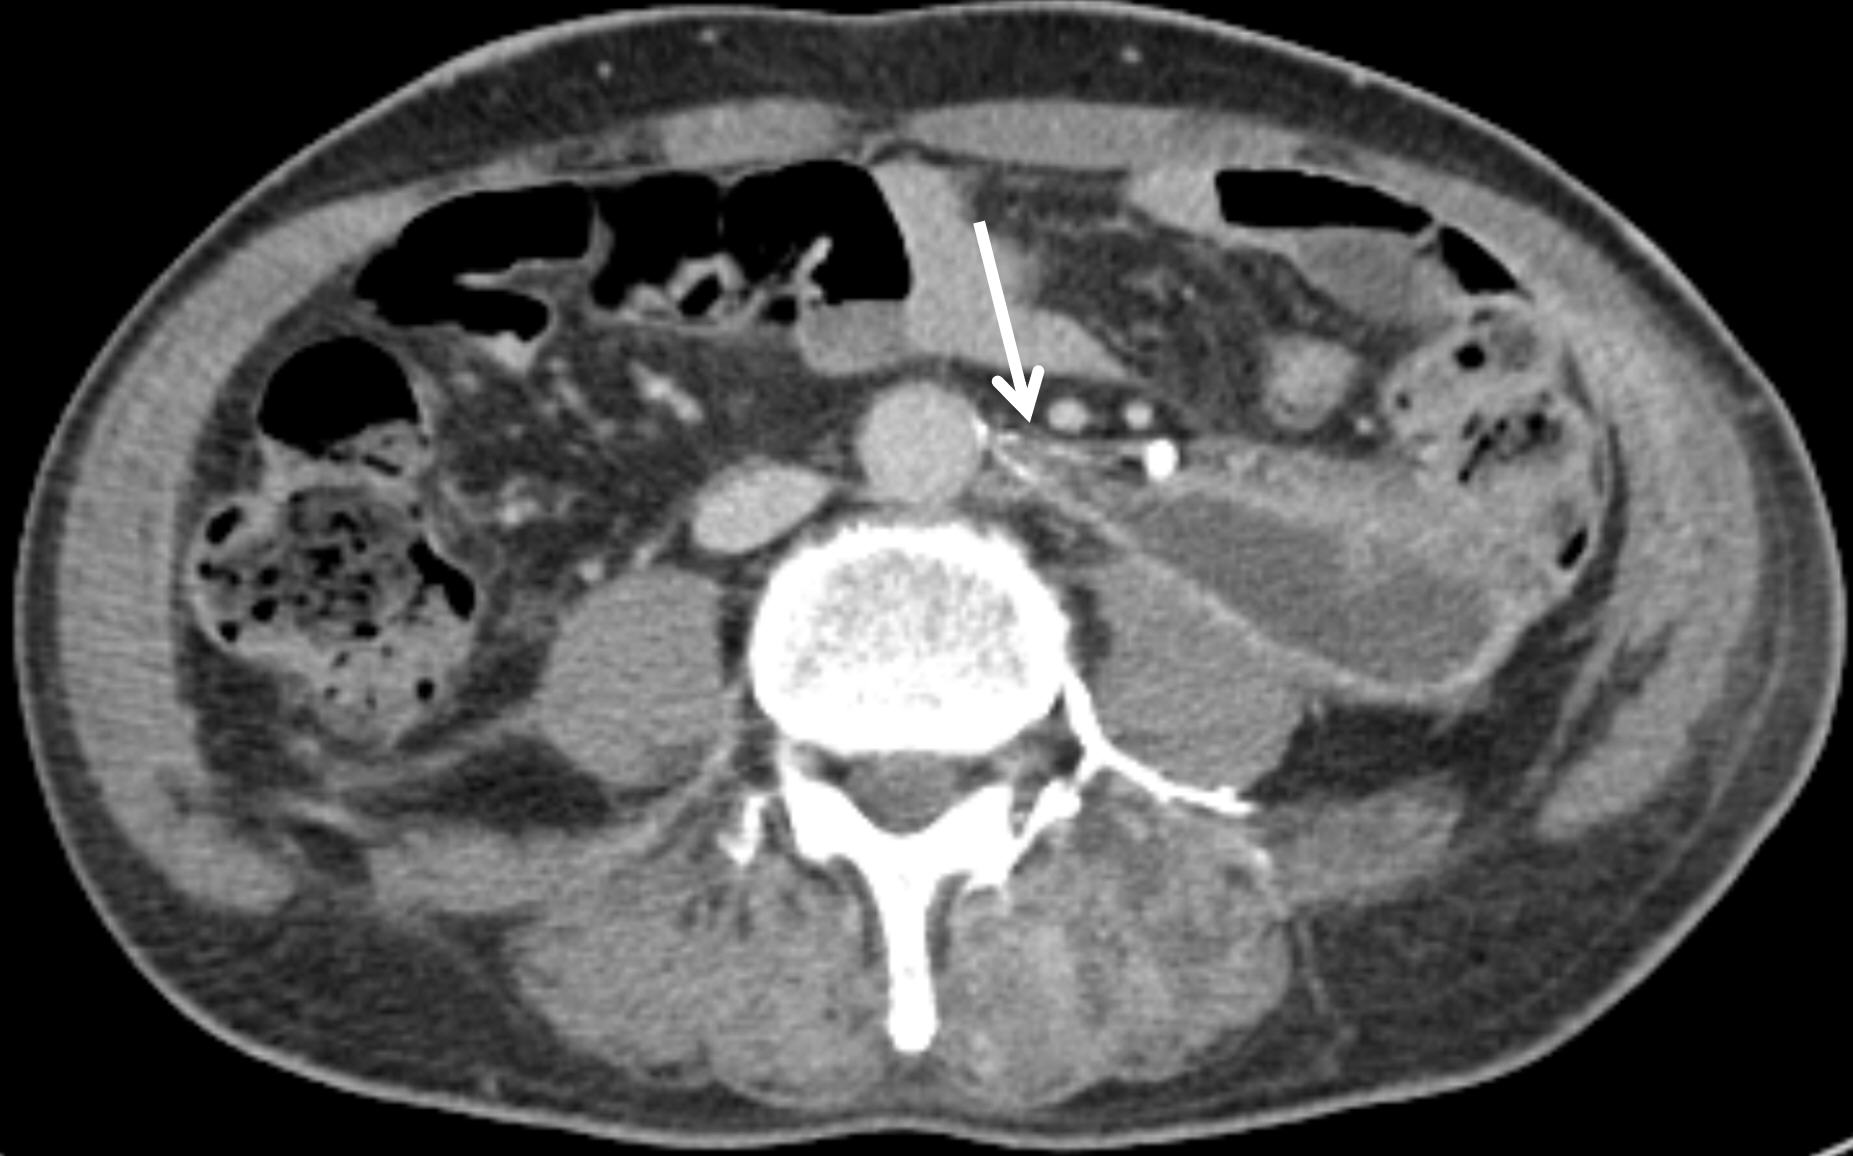

The upper (abdominal) segment of the ureter is primarily supplied by fine ureteric branches originating from the main renal artery. Less commonly, arterial supply may also arise from the abdominal aorta or the gonadal arteries. These vessels approach the ureter medially and bifurcate into ascending and descending branches, forming a longitudinal anastomosis along the ureteral wall [

5] (

Fig. 4). Anatomically, the ureteric artery typically originates laterally from the abdominal aorta. However, in the present case, it appeared to originate anteriorly due to displacement caused by a surrounding hematoma. On follow-up computed tomography, after resolution of the hematoma, the artery was again visualized as originating laterally. This case underscores that an exclusive assumption of a lateral origin from the abdominal aorta may impede the precise identification of the ureteric artery in certain clinical contexts.

Fig. 4.In this schematic drawing of the segmental arterial supply to the ureteric artery, the supplying arteries are depicted as thick black lines: from top to bottom, the renal artery branch, gonadal artery branch, aortic branch, and multiple branches of the internal iliac artery.